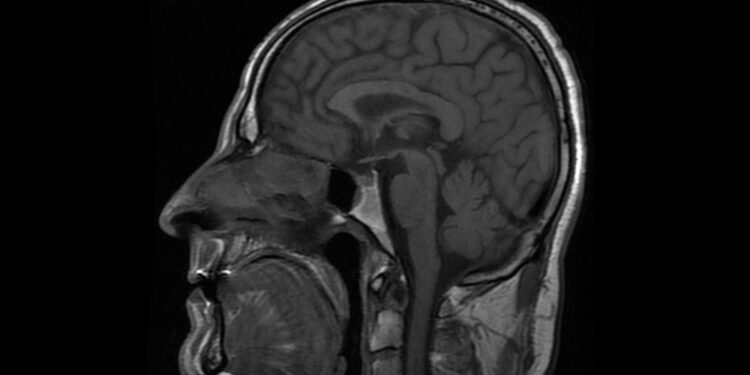

Diagnozei patvirtinti taikomi išsamūs smegenų vaizdavimo tyrimai, dažniausiai – magnetinio rezonanso tomografija (MRT), leidžianti išryškinti menkiausius smegenų struktūrų pokyčius. Vaikams dažnai taikoma lengva nejautra, kad jie būtų ramūs tyrimo metu. Jei pasireiškia priepuoliai, papildomai atliekamas elektroencefalograma (EEG), kuris parodo smegenų elektrinį aktyvumą.